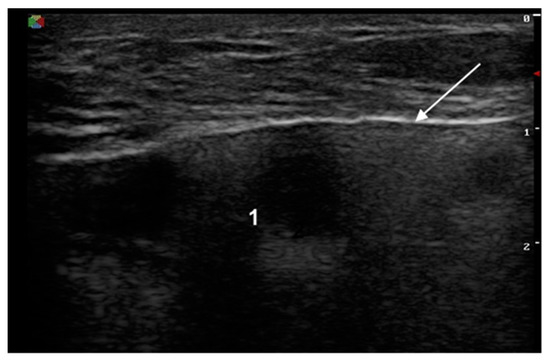

The signs of a ruptured breast implant were an uneven implant shell and inhomogeneous intracapsular echotexture (Figure 2).

Figure 2. Signs of a ruptured implant on ultrasound: white arrow—abnormal shell (one white line is visible); 1—inhomogeneous content.